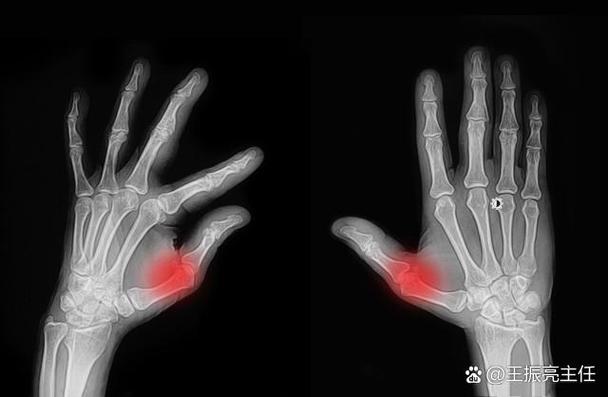

影像学检查

- X光片:可以观察到关节是否有骨质破坏、侵蚀等后期改变。